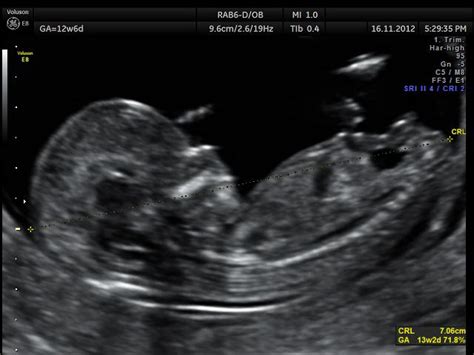

Poiché la datazione basata sulla mestruazione è una stima, la medicina moderna si affida all'ecografia fetale per correggere e validare l'età gestazionale. L'ecografia di datazione è la prima ad essere eseguita ed è ideale se effettuata entro la dodicesima settimana (più precisamente tra la 9+0 e la 15+6).

In questo periodo, l'embrione ha misure abbastanza standardizzate. Se l'età ecografica si differenzia di almeno 7 giorni da quella gestazionale calcolata dall'ultima mestruazione, la gravidanza va nuovamente datata (ridatata). L'American College of Obstetricians and Gynecologists (ACOG) raccomanda di utilizzare la data basata sulle misurazioni ecografiche se differisce dalla data mestruale, con margini di tolleranza che variano a seconda dello stadio della gravidanza:

- Entro 8 6/7 settimane: > 5 giorni di differenza

- Tra 9 e 15 6/7 settimane: > 7 giorni

- Tra 16 e 21 6/7 settimane: > 10 giorni

- Tra 22 e 27 6/7 settimane: > 14 giorni

- Oltre le 28 settimane: > 21 giorni

Una volta eseguita la prima ecografia, la data presunta del parto non viene solitamente modificata in base alle ecografie successive, poiché le stime ecografiche diventano meno accurate con il progredire della gestazione.